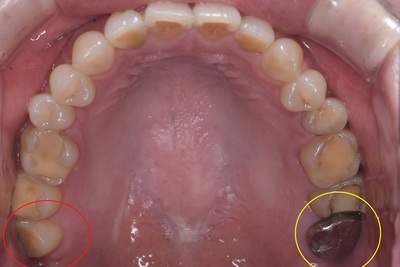

親知らずが虫歯になっている症例

- 抜歯前写真(レントゲン)

- 抜歯前の口腔内写真

- 抜歯した歯の写真

| 年齢 | 40代・男性 |

|---|---|

| 主訴 | 主訴:親知らずを抜きたい 治療部位:左下の親知らず |

| 親知らずの生え方 | 斜めに生えている |

| 抜歯時間 | 説明、麻酔等含めて約60分 |

| 費用 | 合計 約5,400円(保険診療3割負担) ■内訳 約1,900円 CT撮影約3,500円 (2025年2月現在) |

| 抜歯内容 | 左下8番の普通抜歯 |

| 治療方針 | 初診時に親知らずの虫歯を確認しました。 先に別の部位の治療をしていましたが、痛みが出てきたため抜歯を行うこととなりました。 |

| 特記事項 | 抜歯をする前にCTを撮影をし、下歯槽神経との位置を確認した上で抜歯を行いました。 |

| 担当者所見 | 初診のご来院時から、すでに虫歯が大きく進行していました。 ご来院時にお痛みはなかったものの、大きい虫歯でしたので、いつ痛みだしてもおかしくない状態でした。 麻酔が効きづらかったため抜歯に時間を要しましたが、根が折れることなく無事に抜けました。 |